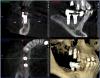

x3m Опубликовано 6 сентября, 2013 Автор Поделиться Опубликовано 6 сентября, 2013 (изменено) тест на витальность сейчас не проводился. мотивировать пациента не хочу - я рассказал свое видение ситуации.послушав авторитетные мнения, рассказал о вариантах на тему и прогнозах.дал ссылку на форум.написал письмо с вопросами автору установки имплантатов.созванивался и общался с этим же автором.как мне показалось, этого вполне достаточно, чтобы пациент самостоятельно принимал решение. теперь о вопросах.1. Где находится имплантат 16? Почему не видно кости?Визуально виден доступ в этой зоне: разрез от 14 до бугра по вершине а/о ...и торчащие заглушки. т.к. от доктора инфы я не получил, подозреваю открытый синус? меня смущает отсутствие кости у 16, реакция слизистой в гайморовой, положение платформы относительно 15 (с оглядкой на будущее протезирование), габариты будущей коронки на 16 (КТ в окклюзии). 2. наличие кортикалки вестибулярно у имплантата в позиции 15 - где она? 3. Четвертый сегмент. 45 и 46-й платформами находились над силизистой.В этот визит проводилось протезирование 4 сегмента.насколько я понял, протезирование (+44 консоль) - временное (пластмассовая облицовка), хотя... для чего оно здесь? вероятно, оно-таки постоянное (пациент не знает, доктор информацию не раскрыл)). Коронки - массивные нависающие края (2-3мм вглубь при зондировании микрорезьбы), формат коронок с отрицательным углом, под балконом - отложения налета, легко кровоточащая десна... еще смущает глубина погружения имплантатов вестибулярно - кмк, в кости лишь половина макрорезьбы... какой прогноз? фото пока выложить не могу, постараюсь на след.неделе. 4. второй сегмент.Что делаем с 27,28? Думается, удаление 27,28 и откр. синус.реакция в гайморовой - затёк из кармана? 5. 36. несколько смущает ось и погружение.хотя изо всего установленного это самый неплохой)) 6. Состояние во фронтальном участке после костной пластики.материал не там, где хотелось бы.остатки под носовым ходом (красным), объема ни вестибулярно, ни по высоте нет.автор предложил имплантацию в этой зоне не рассматривать.Линия улыбки, в принципе, невысокая, но не хочется, чтобы перегружали 11 и 23 мостом с розовой керамикой... Какова вероятность восстановления объема аутоблоками?(желтым указана небная кортикалка). Коллеги, буду благодарен за попунктовые ответы п.с. сорри за много букоФ и картинкоФ Изменено 6 сентября, 2013 пользователем x3m Ссылка на комментарий

Bier Опубликовано 6 сентября, 2013 Поделиться Опубликовано 6 сентября, 2013 открытый синус однозначно, на КТ видно окно, часть материала мигрировала в пазуху, пазуха вся в отеке. Ссылка на комментарий

kriokov Опубликовано 6 сентября, 2013 Поделиться Опубликовано 6 сентября, 2013 похоже по кт, что винт 15 вестибулярно закрутили, и кортикалки там и не будет. Синус почти тотально со снижением пневматизации, чего там полипоз или полипоз и жидкость х\з. По поводу 16- похоже на открытый синус, но графт как то не плотно, и винт похоже только 2 мм за нативную кость цепляется. имхо. Странно, что оператор обьясниться не хочет, у всех косяки бывают, Ссылка на комментарий

Bier Опубликовано 12 сентября, 2013 Поделиться Опубликовано 12 сентября, 2013 1. имплантат 16з стоит своей частью в полости пазухи, выполнен синуслифтинг. Вокруг имплантата виден остеотропный материал слабо рентген контрастный. Своей коронарной частью имплантат стоит в мягких тканях на 4 мм, что делает прогноз на его дальнейшую жизнь сомнительным. 2. имплантат 15 з расположен слишком вестибулярно, кортикальная пластинка либо очень тонкая либо ее нет. Прогноз неблагоприятный.3. Необходимо как минимум перепротезирование. Прогноз оценивать исходя из наличия или отсутствия гноетечения и стабильности имплантатов. Возможно можно ограничиться увеличением ЗКПД и адекватным протезированием. При наличии гнойного перимплантита рекомендовано удаление. Прогноз сомнительный.4.Согласен, удаляем. Реакция в гайморовой может быть и от кармана, а может быть остаточными являениями. Не критичны для синуслифтинга.5.36I я бы сохранил.6.объем кости для имплантации неадекватный. Для восстановления аутоблоки прогноз сомнительный. Я выступаю либо за грамотновыполненный GBR либо за 3D по Кюри. 2 Ссылка на комментарий